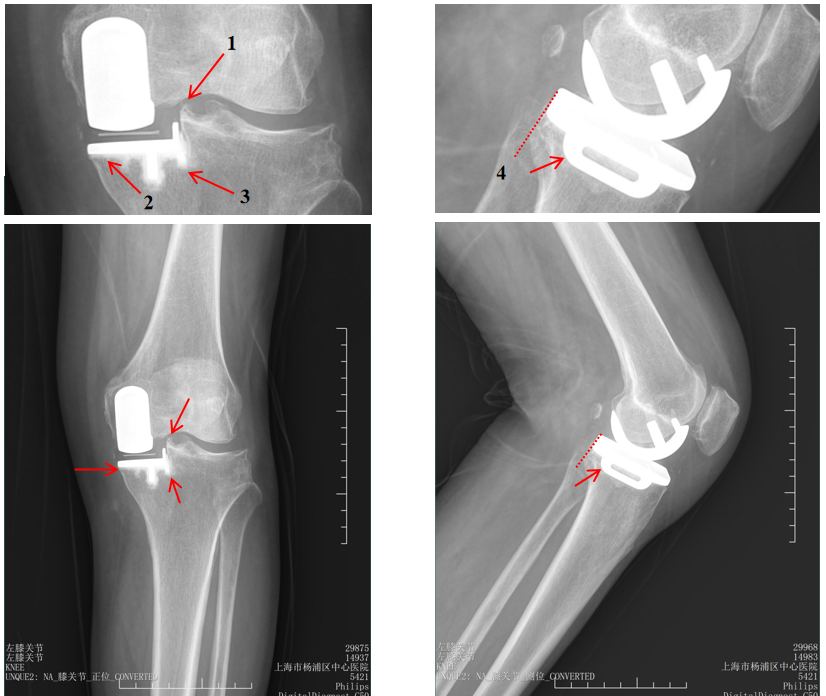

病例1:胫骨假体后倾角度>7°

问题:胫骨假体后倾角度12°,轻度膝外翻

病例1:胫骨假体翻修

UKA to UKA 更换胫骨假体